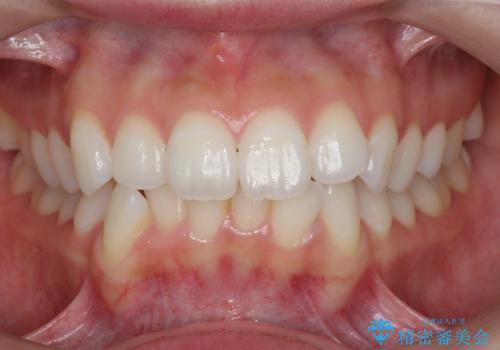

歯を抜かずに後方移動で達成する、前突感の改善

- 前歯が出っ歯のように見えることの改善を求めて来院されました。

当初、セラミックによる治療をご希望されていましたが、相談の結果矯正治療を選択されることとなりました。

マイクロインプラントを用いてしっかりと後方移動を行ったことで前歯の角度は改善され、口元もすっきりと仕上げることができました。